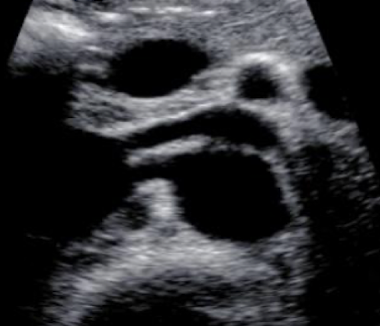

LRV and RRA locations

LRV

anterior to AO; posterior to SMA

runs from left kidney to IVC

RRA

posterior to IVC (excuse me)

runs from AO to RK

??